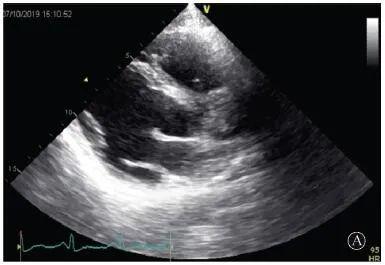

患者入院后無(wú)特殊不適,心率70次/min,血壓110/60 mmHg,心功能Ⅱ級(jí)。查血常規(guī):血紅蛋白139 g/L,白細(xì)胞7.39×109/L,血小板221×109/L。尿常規(guī)、便常規(guī)+潛血均正常。生化:丙氨酸氨基轉(zhuǎn)移酶38 U/L,白蛋白47 g/L,鉀3.9 mmol/L,肌酐(酶法)65 μmol/L,總膽固醇3.52 mmol/L,低密度脂蛋白膽固醇2.08 mmol/L。CK:1256→487 U/L,CK-MB 9.7→3.8 μg/L,cTnI 85.90→68.50 pg/ml。N末端B型利鈉肽原70 pg/ml。CK同工酶電泳:肌酸激酶MM質(zhì)量100.0%(此時(shí)CK-MB已正常)。血沉1 mm/第1小時(shí),高敏C反應(yīng)蛋白1.61 mg/L;補(bǔ)體:C3 0.876 g/L,C4 0.174 g/L。免疫球蛋白:IgG 9.52 g/L,IgA 1.73 g/L,IgM 0.62 g/L。血清蛋白電泳未見(jiàn)M蛋白。糖化血紅蛋白5.1%。乳酸(運(yùn)動(dòng)前)1.1 mmol/L,乳酸(運(yùn)動(dòng)中)6.6 mmol/L,乳酸(運(yùn)動(dòng)后)7.8 mmol/L。肌炎抗體譜:抗PM-SCL75(+),余均(-)。心電圖:aVL、V5、V6導(dǎo)聯(lián)T波倒置(圖2)。冠狀動(dòng)脈CT未見(jiàn)明顯異常。超聲心動(dòng)圖:左室舒張末內(nèi)徑55 mm,左室收縮功能減低,心尖部、左室壁普遍運(yùn)動(dòng)減低,以左室下后壁為著,左室下后壁肌小梁明顯增多可見(jiàn)隱窩,疏松層與致密層之比為1.7;左室射血分?jǐn)?shù)(雙平面)45%;右冠狀動(dòng)脈開(kāi)口6.5 mm,開(kāi)口處未見(jiàn)明確瘤樣擴(kuò)張(圖3)。

協(xié)和疑難︱第67例:臨床表現(xiàn)胸痛伴肌酸激酶升高

A:胸骨旁長(zhǎng)軸平面,左室舒張末內(nèi)徑略增大,室壁無(wú)明顯增厚;

B:胸骨旁左室短軸切面心尖水平,可見(jiàn)心肌肌小梁增多,其內(nèi)可見(jiàn)隱窩(箭頭所示)

圖3 患者入院后超聲心動(dòng)圖